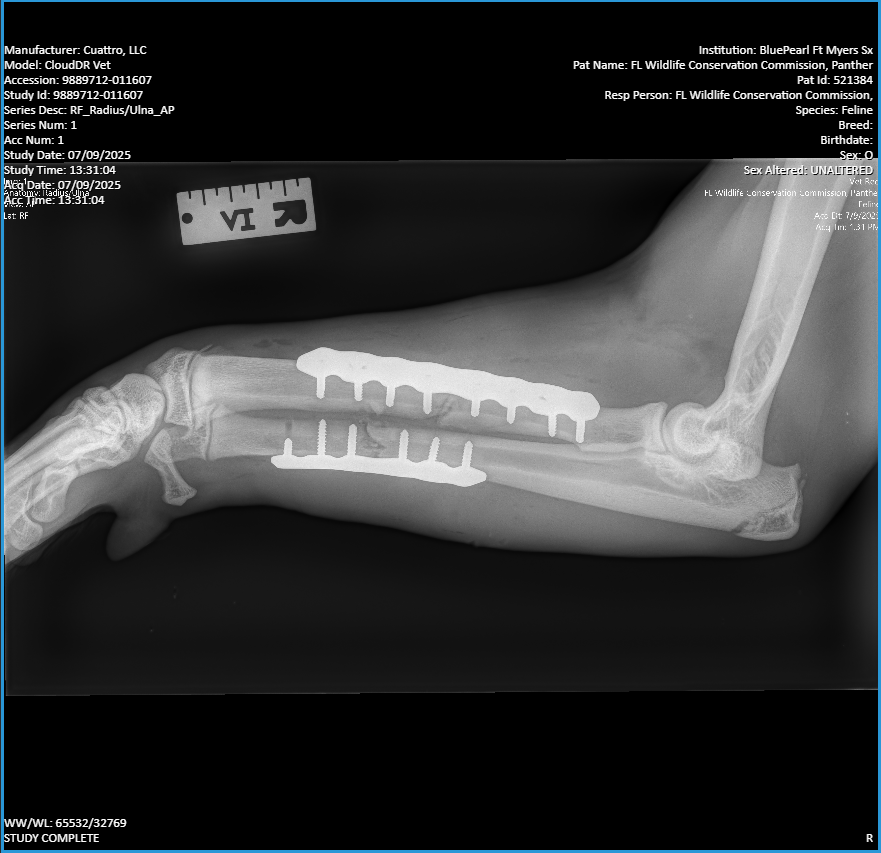

They had an injured young panther named Loper in need of surgery. The animal had been hit by a car in Fort Myers and fractured its radius and ulna. The fractures were repaired using orthopedic plates.

An XRay of Loper’s fractures, the Florida panther recovering at ZooTampa. Photo courtesy of ZooTampa.